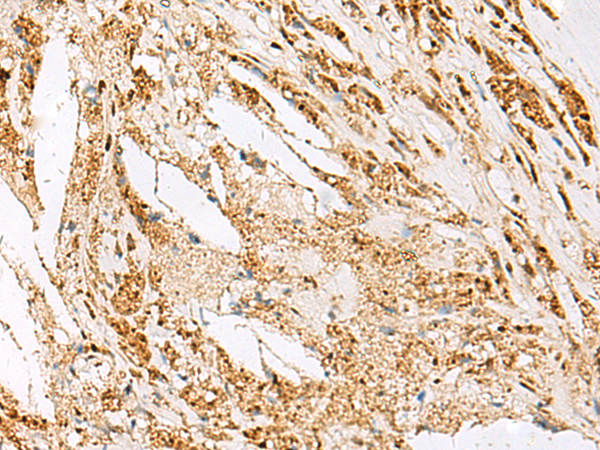

IHC (Immunohistochemistry)

(Immunohistochemistry of paraffin-embedded Human thyroid cancer tissue using DNPEP Polyclonal Antibody at dilution of 1:60(×200))